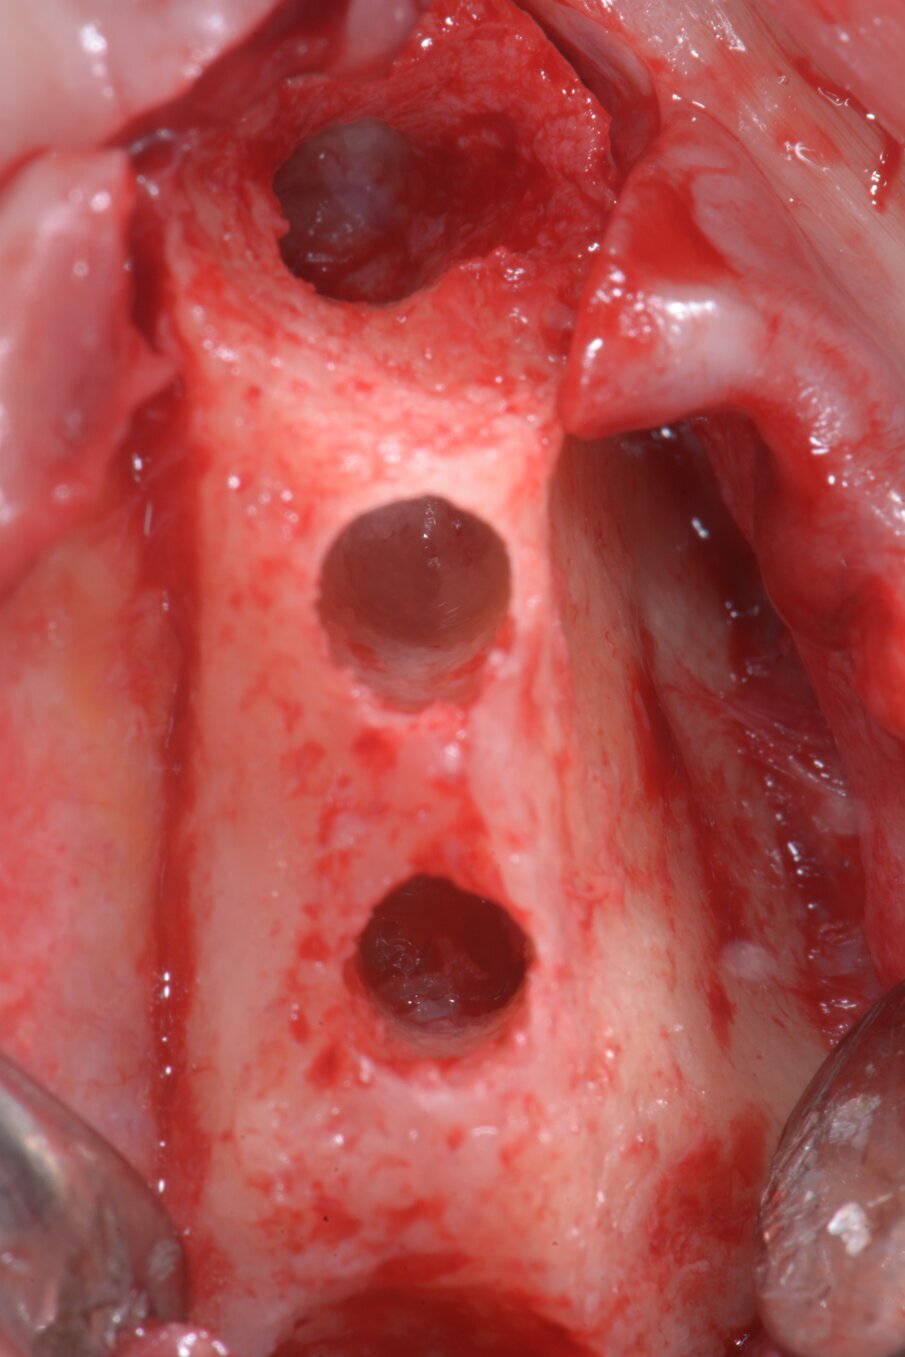

Quando le frese Densah successive avanzano nell’osteotomia, l’osso viene spinto (o densificato) verso l’estremità apicale e comincia a sollevare gradualmente la membrana di Scheneider con l’osso autologo compattato. Utilizzare sempre le frese con movimento di “pompaggio” e abbondante irrigazione, al fine di non surriscaldare l’osso. Per raggiungere una maggiore profondità verticale e il sollevamento graduale della membrana senza perforazioni si consigliano incrementi di 0,5 1,0 mm per fresa, fino ad ottenere la lunghezza e il diametro finale desiderato. Si ricorda che le frese in successione possono raggiungere un sollevamento della membrana di massimo 3 mm. Vista la scarsa qualità e quantità ossea residua del caso in questione, pur usando le frese Densah in modalità di osseodensificazione non si riesce a mantenere una integrità ossea della porzione apicale dei siti osteotomici (Fig. 5). Nei casi di incrementi superiori a 3 mm si può collocare all’interno dell’osteotomia del materiale da innesto, utilizzando l’ultima fresa con velocità di 150-200 giri/min senza irrigazione e in senso antiorario, per compattarlo all’interno dell’osteotomia. In questo caso si posizionano delle membrane di PRF all’interno dei siti osteotomici, così che la membrana di Schneider venga sollevata idrostaticamente con leggere pressioni del PRF (Fig. 6). Finita la fase di preparazione dei siti osteotomici si può procedere all’inserimento implantare a 20 giri/min e 50 Ncm di coppia (Fig. 7). Si esegue a questo punto un innesto di osso eterologo tipo “L-PRF-block”7 per incrementare il volume della zona vestibolare (Fig. 8). Sull’innesto vengono posizionate delle membrane di PRF assottigliate (Fig. 9) e una ulteriore membrana riassorbibile viene posizionata sopra il PRF per assicurare l’immobilità del tutto (Fig. 10). Si procede con l’esecuzione di scarichi di rilascio periostali, per avere un lembo privo di tensioni muscolari (Fig. 11). Infine, viene eseguita una sutura con filo 5 zeri riassorbibile monofilamento (Fig. 12). Nell’immediato post-operatorio viene eseguita alla paziente una CTCB di controllo. Come si può notare dalle sezioni della stessa, la membrana sinusale non risulta perforata, ed è sollevata sugli impianti (Figg 13, 14). Notare la neoformazione ossea apicale agli impianti a 5 mesi dall’intervento (Fig. 15).

Fig. 5 - Visualizzazione macroscopica delle porzioni apicali dei siti osteotomici preparati con Densah kit. Si intravede la membrana di Schneider intatta.

Fig. 6 - Posizionamento membrane di PRF nei siti osteotomici.